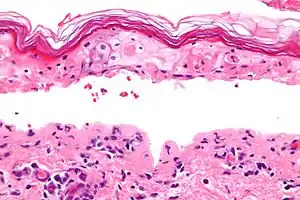

Pathology

SJS, like TEN and erythema multiforme, is characterized by confluent epidermal necrosis with minimal associated inflammation. The acuity is apparent from the (normal) basket weave-like pattern of the stratum corneum.